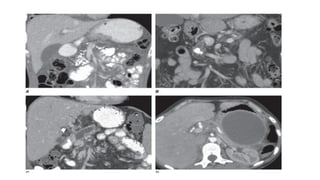

• A. Numerous punctate calcifications involving the pancreatic

parenchyma in the head and body.

• B. A moderate-sized calculus visualized in the pancreatic duct with

associated ductal dilation.

• C. Significant pancreatic duct dilation and adjacent parenchymal

atrophy secondary to a pancreatic duct stricture (which is not well

seen on this scan).

• D. A large unilocular, encapsulated cyst in the tail of the pancreas

consistent with a pseudocyst from prior pancreatitis. Note adjacent

pancreatic parenchymal atrophy.

• A. Numerouspunctate calcifications involving the pancreatic parenchyma in the head and body. • B. A moderate-sized calculus visualized in the pancreatic duct with associated ductal dilation. • C. Significant pancreatic duct dilation and adjacent parenchymal atrophy secondary to a pancreatic duct stricture (which is not well seen on this scan). • D. A large unilocular, encapsulated cyst in the tail of the pancreas consistent with a pseudocyst from prior pancreatitis. Note adjacent pancreatic parenchymal atrophy.